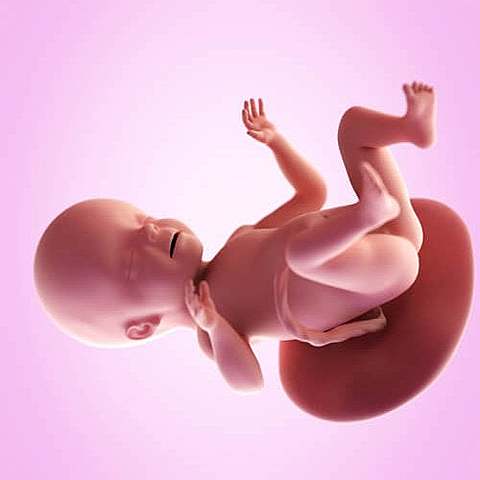

• Semana 22

Semana 22

En la semana 22 de embarazo (20 semanas desde la concepción) tu bebé mide 27 centímetros y pesa casi 500 gramos.

Al mirarlo, tiene prácticamente el aspecto del de un bebé a término, pero todavía necesita ganar peso. Su grasa corporal representa el 1% de su cuerpo, pero de ahora en más irá ganando capas de grasa, la cual le ayudará a regular su temperatura corporal.